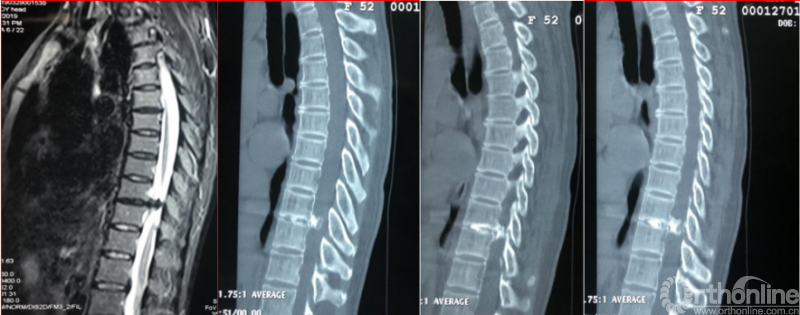

术前资料

术后影像学资料

术后第二天资料

术后8个月资料